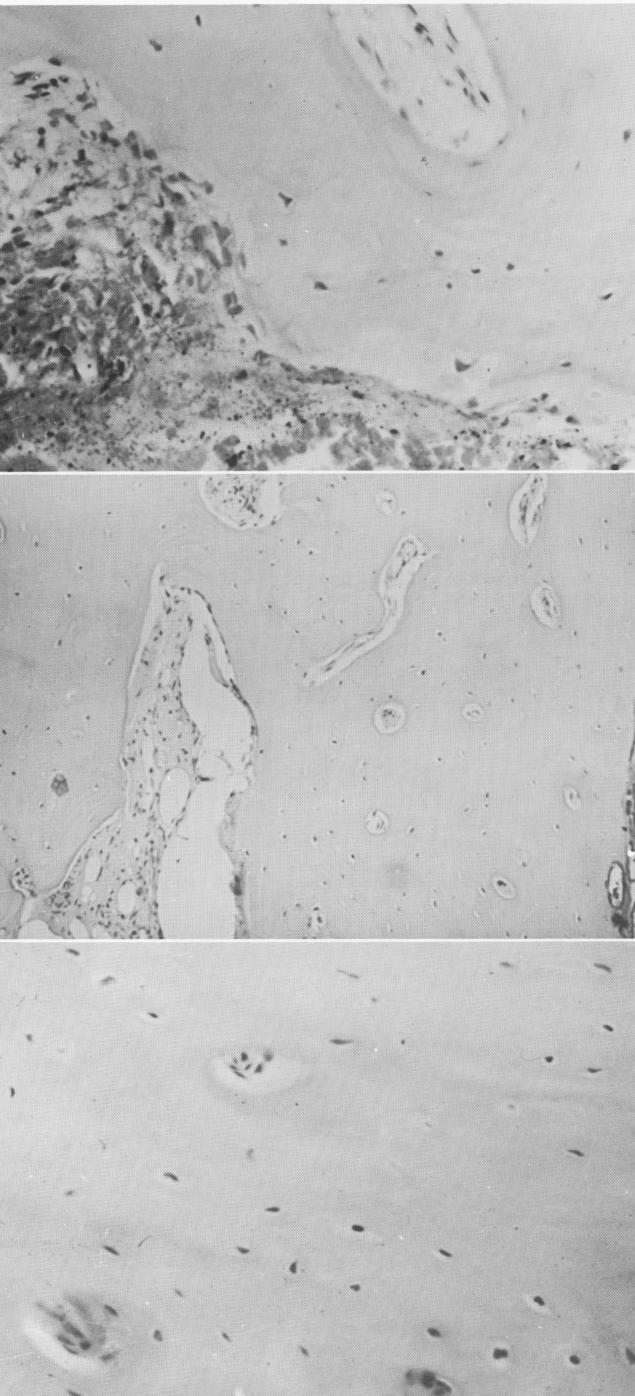

Fig. 4-56. Evidence of surgical hemorrhage in a bone section.

Fig. 4-57. The inner aspect of bone appears to be vital.

Fig. 4-58. Under higher magnification, the osteocytes are clearly demonstrated.

1  Surgical hemorrhage in bone section near vent plant implant site